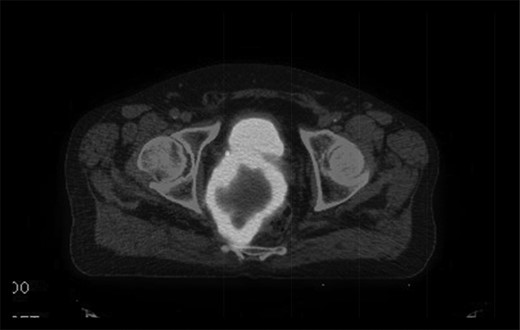

The multidisciplinary team review advised neoadjuvant treatment with imatinib mesylate and further reassessment. Repeat MR pelvis and staging PET CT abdomen, thorax and pelvis were then performed. These showed a large extra-luminal tumour with downsizing in tumour bulk (6 × 5.7 × 5.4 cm) (Figs 3–5) but in close approximation with the right seminal vesicle.

T2-weighted axial images after 3 months of imatinib mesylate therapy. The mass has shown a significant reduction in size (white star).